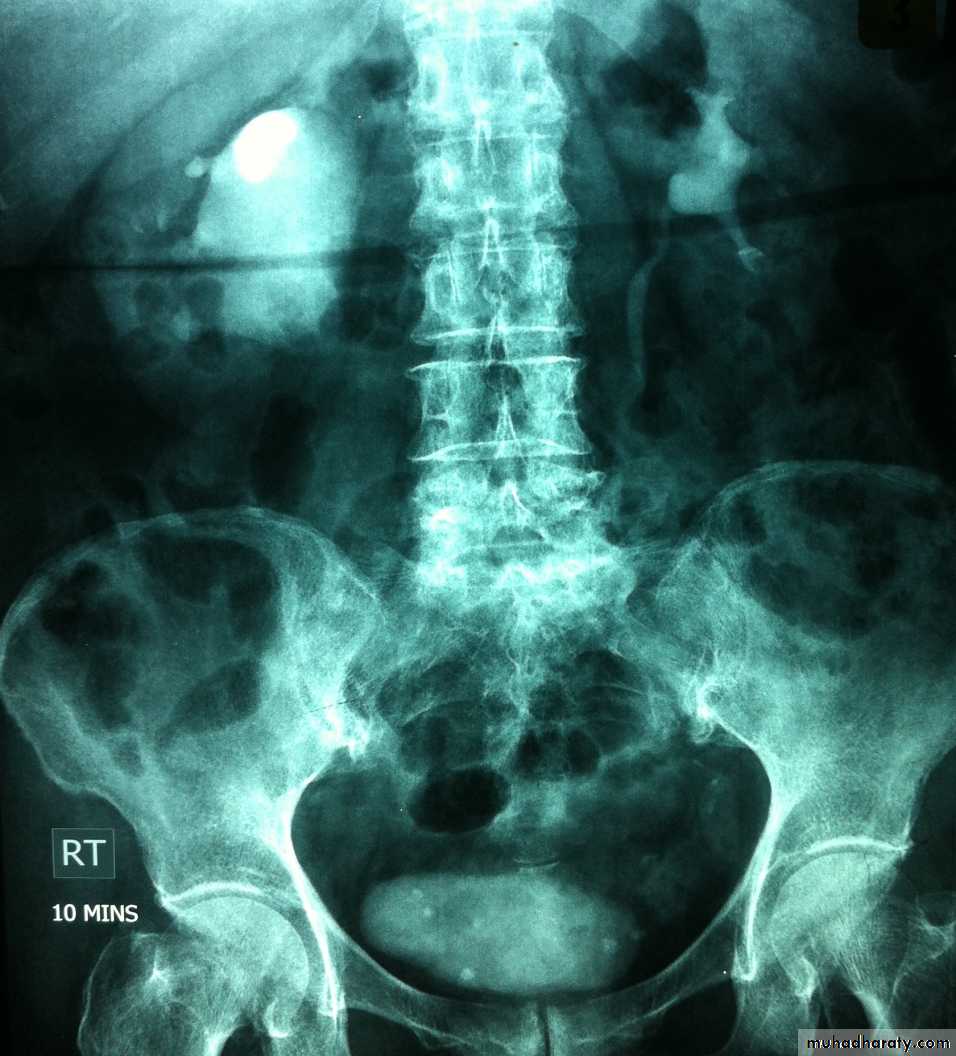

Horse shoe kidney -Kidneys may fail to separate.

-Almost invariably the lower poles remain fused.

-The kidneys axes are more parallel to the spine and malrotated.

-Diagnosis can be made by plain x-ray in some cases.

-US, CT scan and MRI can better demonstrate the anatomy and morphology hence the diagnosis.

-May be an incidental finding.

-PUJ obstruction and calculi formation are common .

IVU shows

1. The kidneys at low position .

2.Close to the spine with long axis parallel to the spine .

3. Malrotation manifested by medially directed calyces.

4- The renal pelvis and ureters are anterior and lateral in position .

urinary system